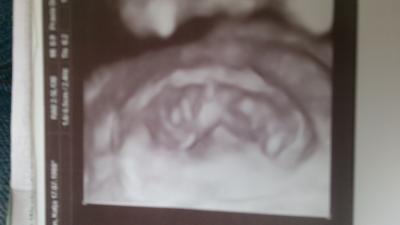

Hallo, ich durfte heute auch zum FA. Bin heute bei 10+4. Dem krümel gehts toll. 3,6cm ist es groß. Hat schön gestrampelt. Und das beste ist das mein hämatom verschwunden ist und ich habe mein kind in 4D gesehen. Toll! Und ein schönes 4D BILD habe ich auch bekommen. Lg

Bild zu auch beim FA :-) - Forum für April - Mamis